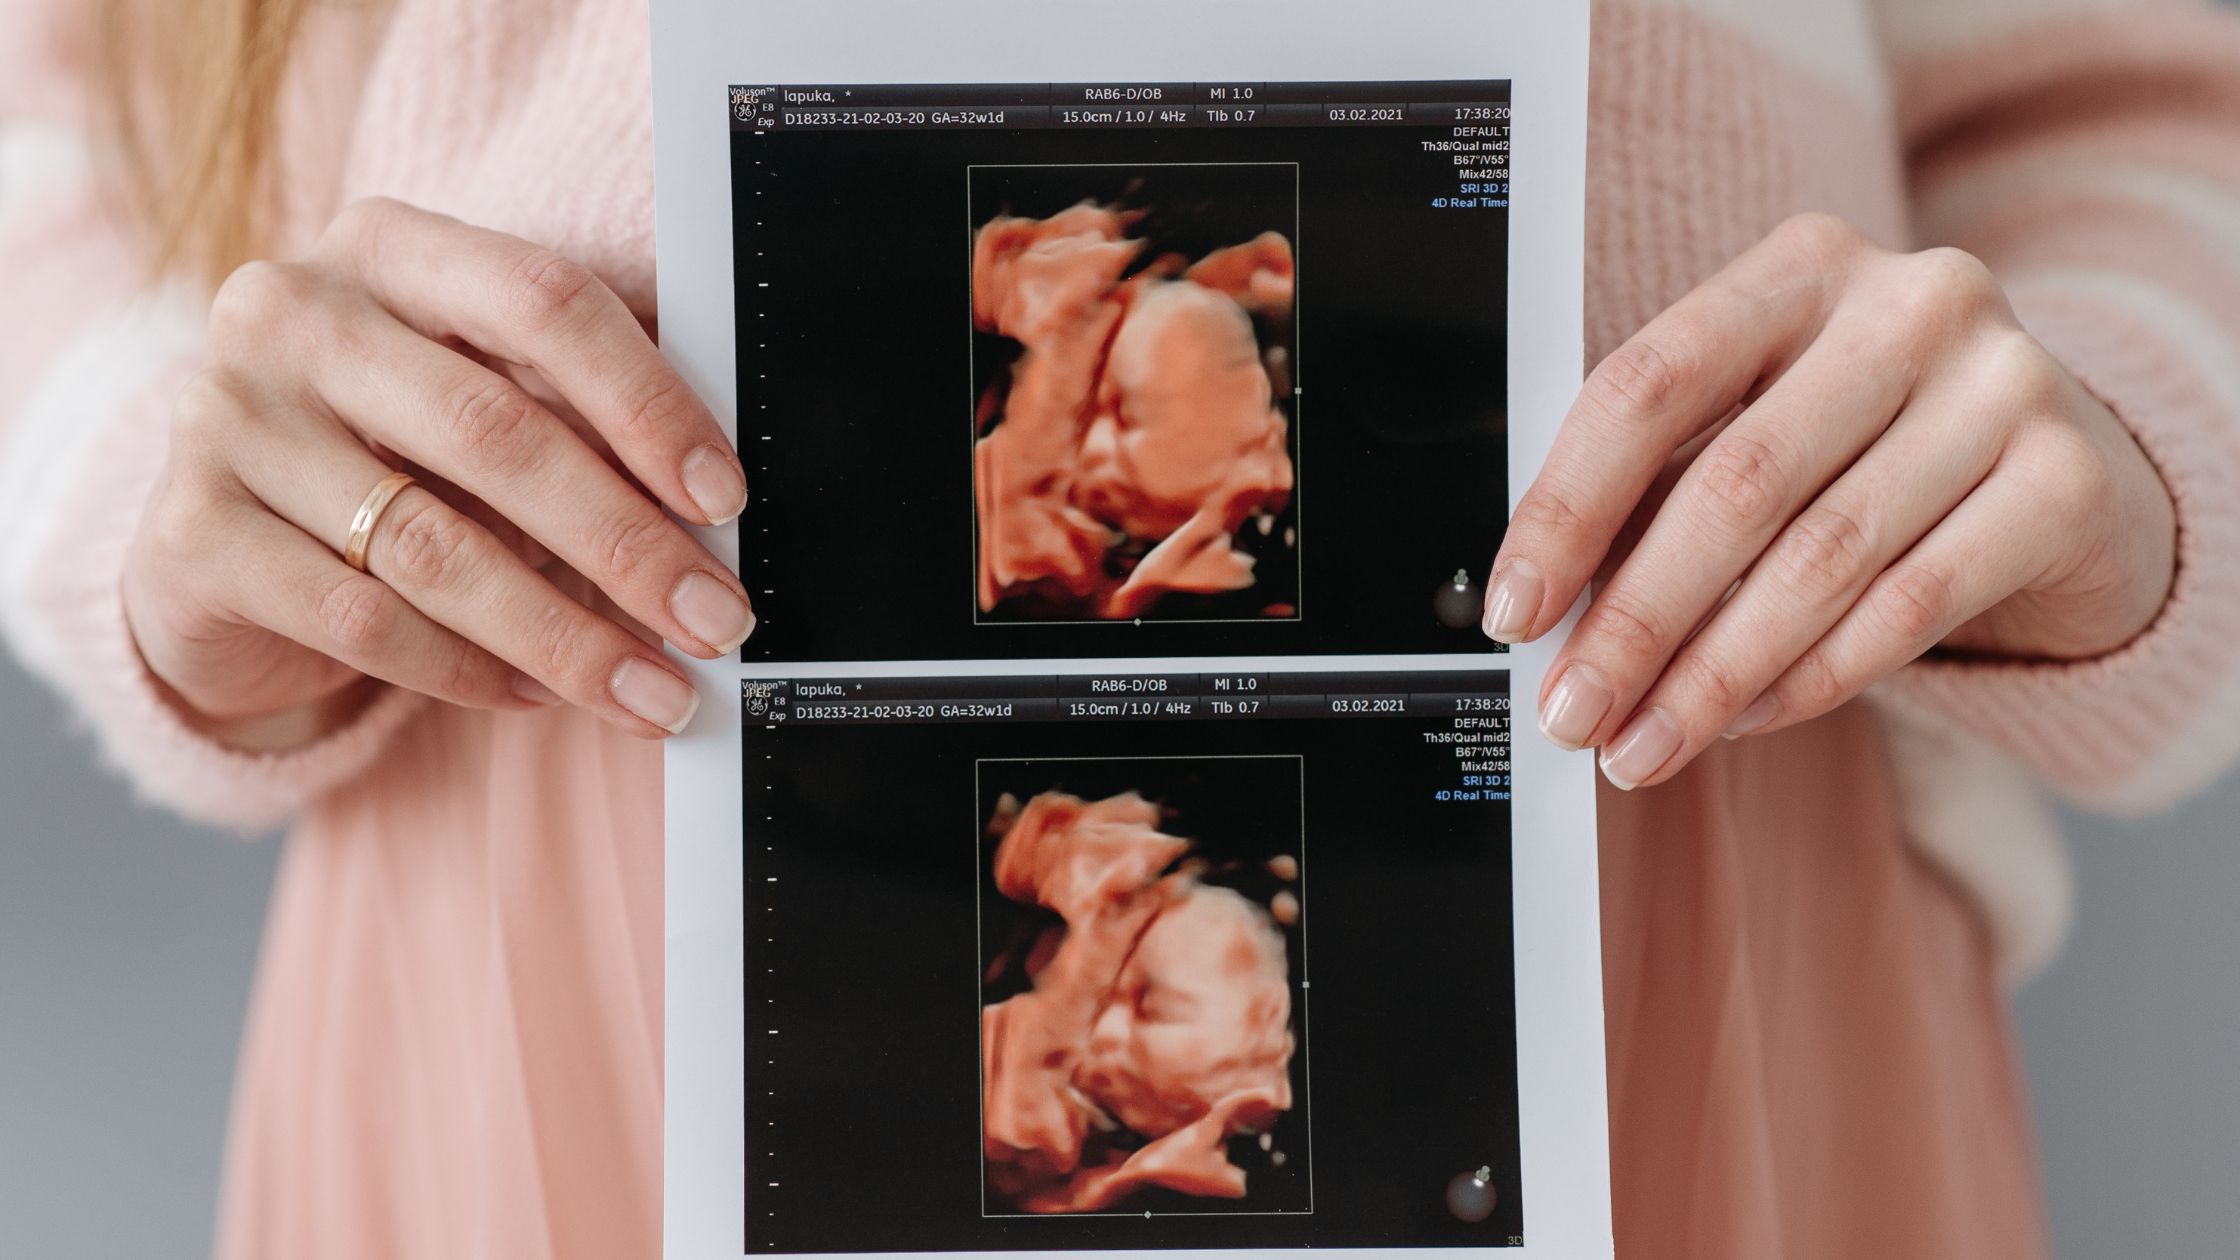

Q1: Is the fetus at one month visible on ultrasound?

At one month, the embryo is extremely small—an ultrasound may not yet show a fetal image clearly.